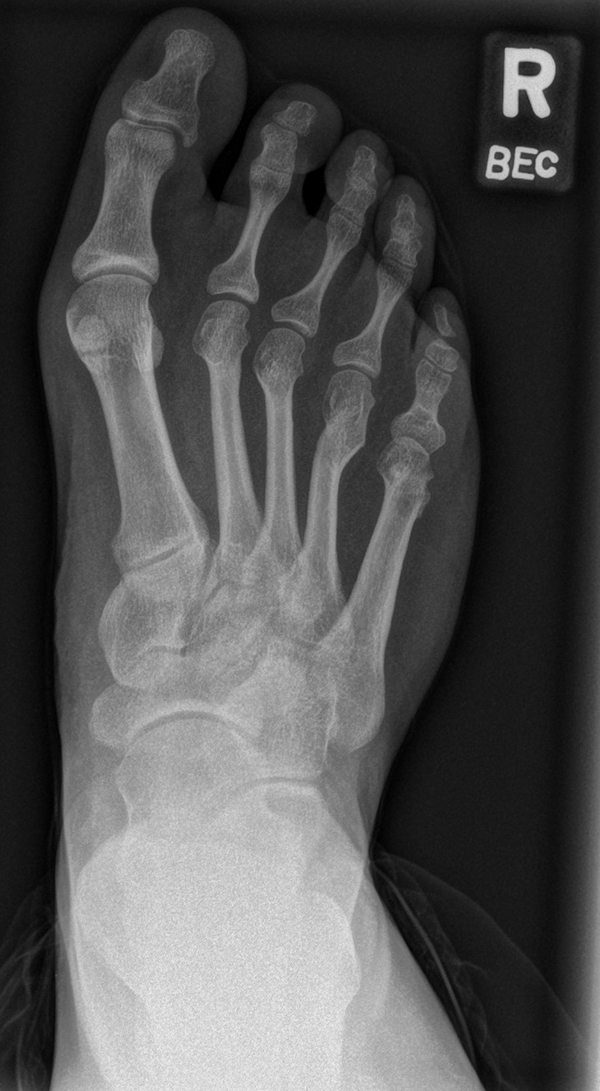

Chevron Osteotomie

Die Chevron Osteotomie 1 ist ohne Komplikationen am wachsenden Skelett durchführbar. Das Metatarsale I besitzt distal keine Wachstumsfuge, die geschädigt werden könnte. Die „französische Methode nach Marc Elkaim“ eignet sich für Kinder ganz besonders (Abb. 28).

Abb. 28 a-g: Radiologischer Verlauf einer Chevronosteotomie nach dem Verfahren von M. Elkaim mit prä- (a-c drei unterschiedliche Ansichten) und intraoperativen Röntgenbildern in zwei Ansichten (d-e) sowie postoperativ zwei Ansichten (f-g).

Sie wird über eine eigene Tapetechnik fixiert und kann bei einem erhöhten Intermetatarsale-Winkel alternativ zur Scarf-Osteotomie durchgeführt werden. Nachteile der Methode sind eine deutliche Verkürzung durch die Fräse sowie eine starke Plantarisierung des Metatarsale I Köpfchens. Um die Verkürzung zu vermeiden, wird verlängernd in Richtung des Metatarsale II Köpfchens (nicht wie offen in Richtung Metatarsale IV Köpfchen) osteotomiert. Gleiches gilt für die starke Plantarisierung, die durch den Knochenverlust der Fräse entsteht. Die Korrektur eines kindlichen oder jugendlichen Hallux valgus ist mit der Methode ansonsten suffizient durchführbar. Wird verkürzt, muss ausreichend plantarisiert werden, um eine Transfer-Destabilisierung MT II-IV zu vermeiden.

Die MICA-Technik sollte bei geschlossenen Fugen mit einem weitem intermetatarsale Winkel durchgeführt werden. Die dafür typische Verschraubung der Osteotomie kann bei geschlossenen Fugen ohne Probleme erfolgen. Diese Osteotomie kann gut mit einer Akin- und den beschriebenen Kleinzehen-Osteotomien kombiniert werden.